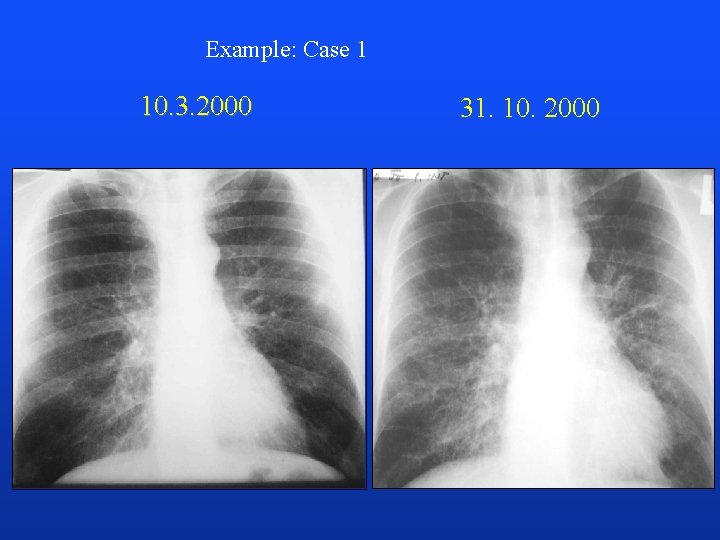

Example: Case 1 10. 3. 2000 31. 10. 2000

CT, brain 3. 11. 2000 Autopsy: lung CA, carcinomatous lymphangiopathy, non-infectious (marantic) endocarditis, peripheral embolization